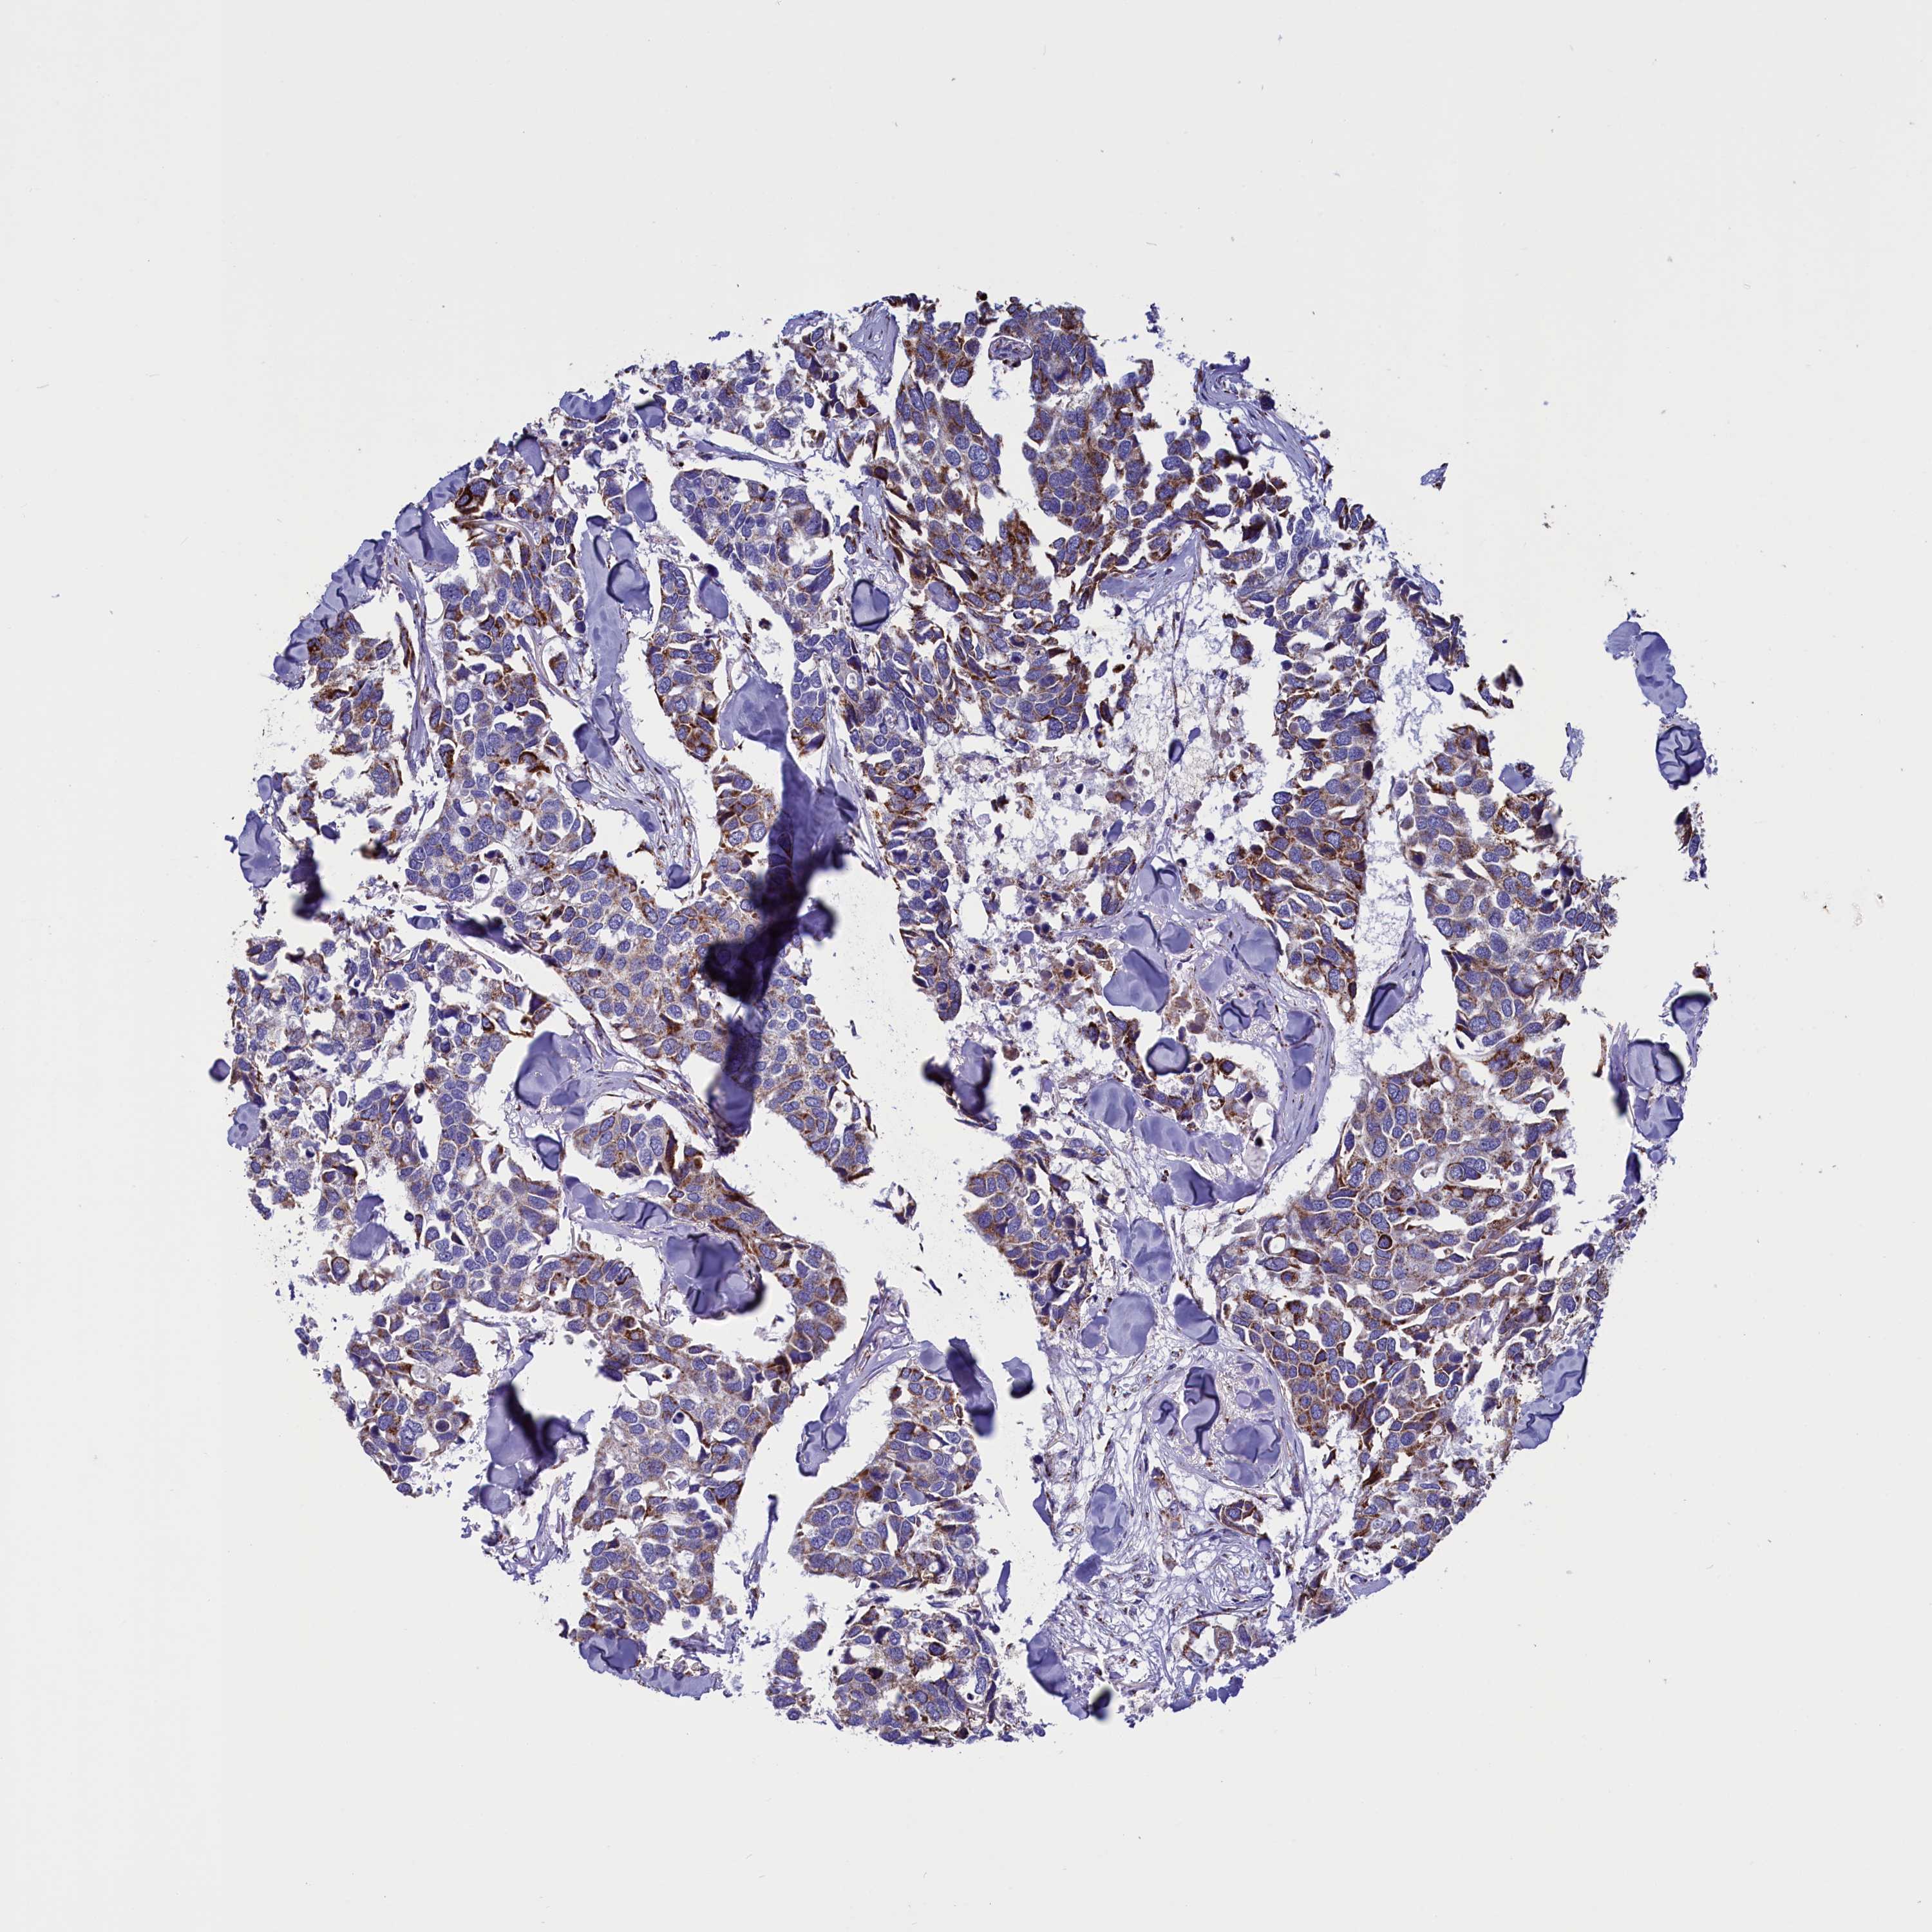

CANCER BREAST CANCER Show tissue menu

BRCA TCGA BRCA VALIDATION PROTEIN EXPRESSION